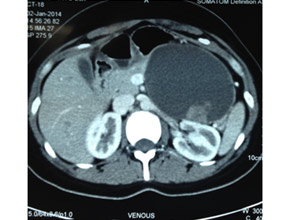

Large Neuroendocrine tumour in pancreatic head